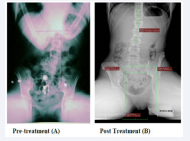

Figure 14 (A): Pre-treatment radiograph of the lumbopelvis in the coronal plane, standing, the sacral base was 18 mm low on the left, and the lumbar scoliosis measured  13 degrees. (B): Post treatment, with a 25 mm heel lift and CFOs in place, the sacral base is level, and the lateral angularity of the lumbar spine is reduced to 9 degrees

For the same subject photographic and radiographic studies were compared, pre- and post treatment, standing (Figures 14,17,19) and seated (Figure 15). These studies show clearly the large improvement in posture where these multi-factorial therapeutic methods are fully applied.